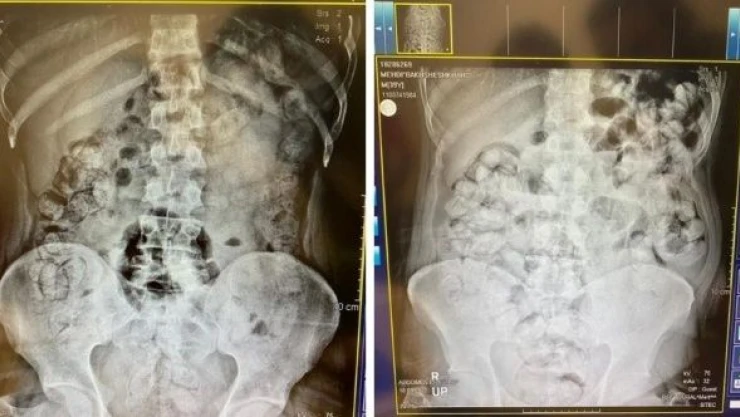

Çekilen röntgen filmlerinde şüphelilerin vücutlarında 62 kapsül eroin ve 210 kapsül afyon sakızı olduğu tespit edildi.

Röntgen çekimlerinde uyuşturucu kapsüllerinin şüphelilerin neredeyse iç organlarının her tarafına yayıldığı belirlendi. Doktor ve polis, vücutta tek seferde bu kadar yüklü miktarda uyuşturucu görmenin şaşkınlığını yaşadı.Gözetim altına alınan ve röntgenleri çekilen şüphelilerin vücudundan parça parça 'dışkılama' yöntemi ile uyuşturucular çıkarıldı. Zanlıların hastanedeki işlemleri sürerken Narkotik Suçlarla Mücadele Şubesi ekiplerinin teknik ve fiziki takiplerinde, benzeri yöntemle yine aynı güzergahtan uyuşturucu götürüleceği bilgisi alındı. Bunun üzerine uygulama noktasında durdurulan bir otobüste, koltukta oturma şekilleri ile hal ve hareketlerinden şüphelenilen İran uyruklu Masoud T. ve Soleman O. gözaltına alınıp hastaneye götürüldü.

Yapılan kontrollerde ve röntgen çekimlerinde, şüphelilerin vücutlarından 411 kapsül afyon sakızı olduğu belirlendi.